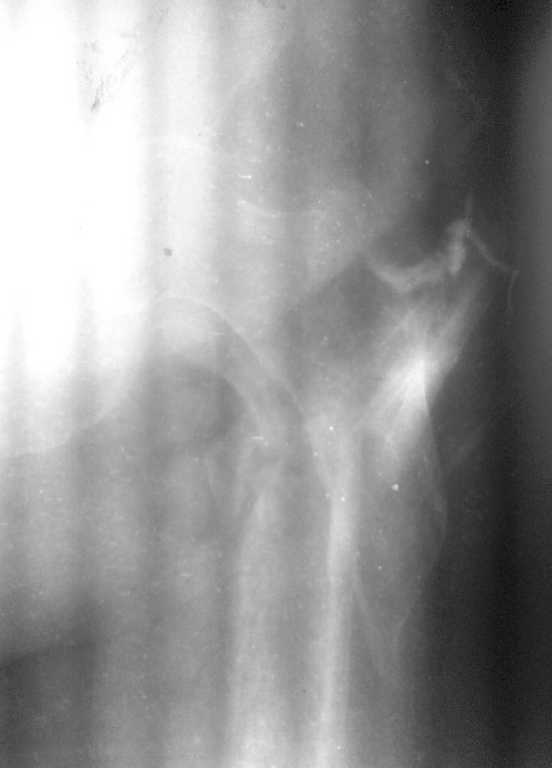

В субботу проведна спица за бугристость ББК, вес 10 кг. Сегодня контрольные снимки - видимого удлинения в соотношении фрагментов нет, патологическая подвижность осталась. Больная тяжело переносит вынужденное положение, беспокоит боль в области перелома. Свищ с воскресенья не функционирует, признаков воспаления в проксимальном отделе бедра нет, лабораторные показатели в норме.

Малый вертел с небольшим фрагментом кортикала отломан.

Место перелома открыли, фрагменты в рубцах, каналы закрыты, кость “сахарная”

Освободили от рубцов, каналы открыли, скусили 1см острого участка проксимального фрагмента для репозиции, заштифтовали без использования молотка, заблокировали дистально 3 винтами (один винт в сагитальной плоскости) и проксимально 2 винта.

Воспользовались слоником для сагиттальной блоктровки, всё легко получилось, спасибо, Anton Kovalenko, за такой ценный совет!